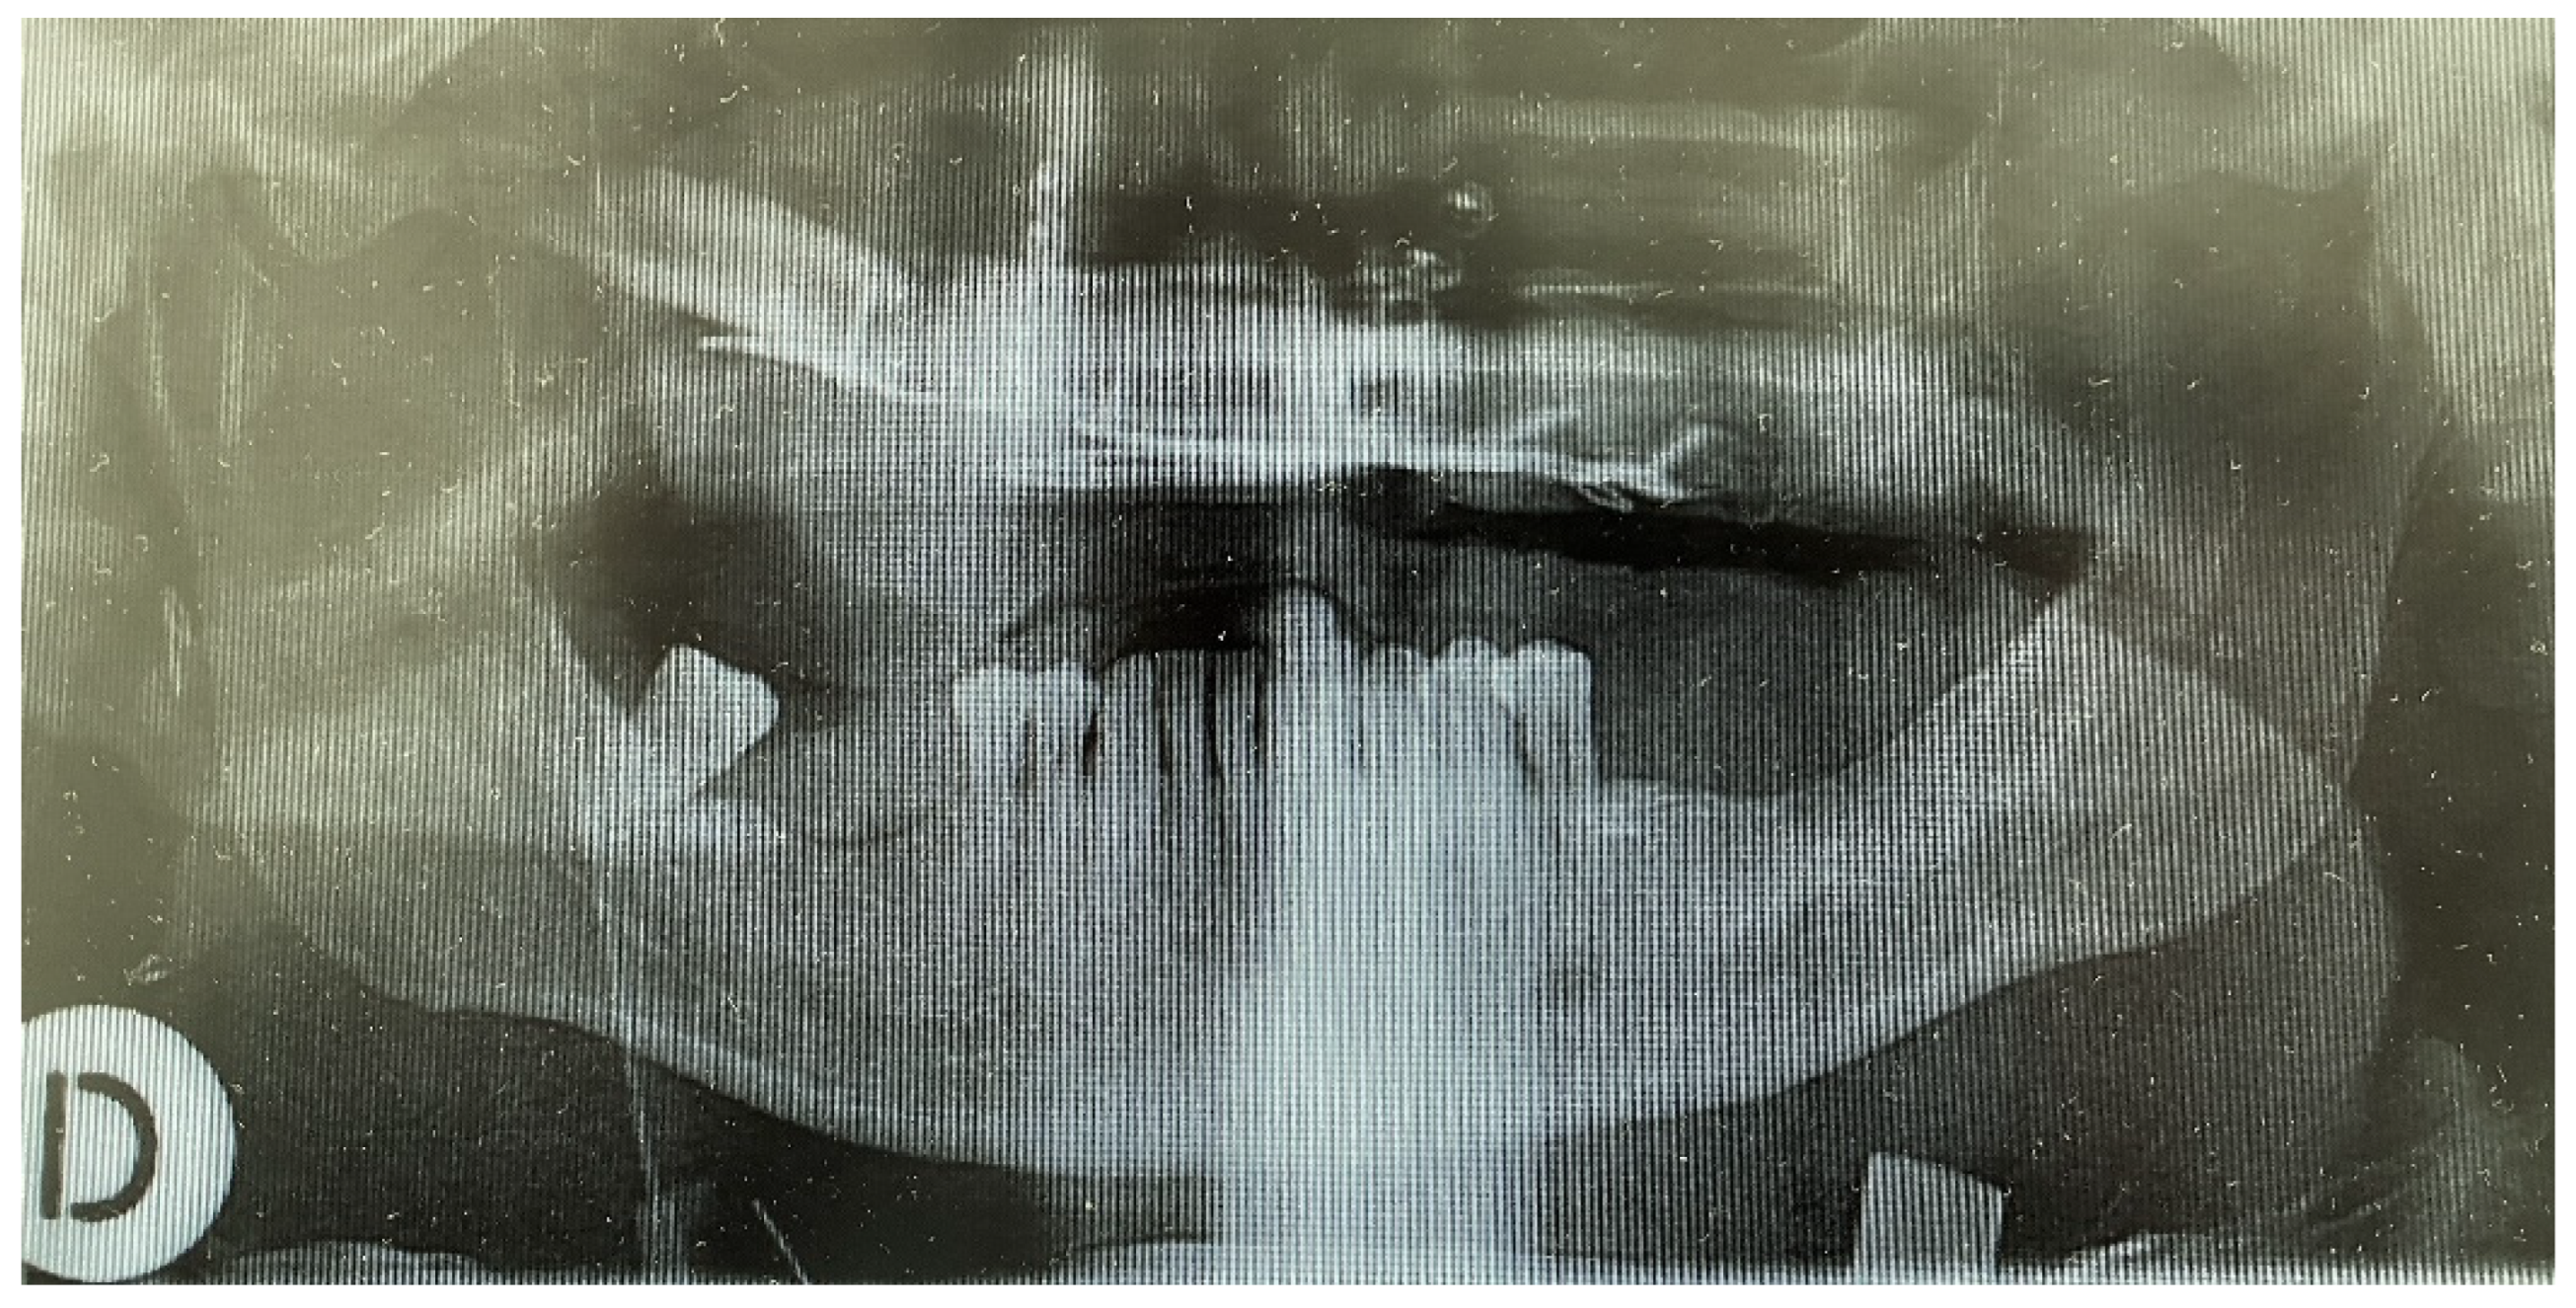

Figure 6.

Post reconstruction panoral X-ray (The day after surgery).